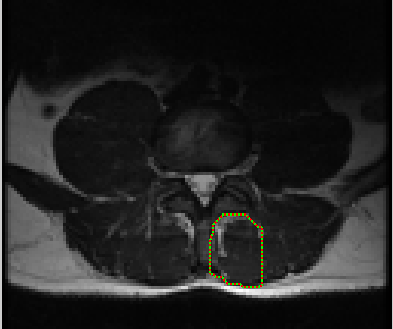

The first step is selecting the region of interest (ROI) from the MRI-defined lumbar muscles, which can be any among the erector spinae (ES) muscles, lumbar multifidus muscles (LMM) or psaos muscles, located either on the right or the left side of the spinal column [2, 5]. The user has to define the ROI by plotting a mask over the input image using livewire technique [21], as shown in Figure 2.

The livewire (or intelligent scissors) [21] is a semi-automatic image segmentation technique that allows the user to interactively select the ROI on an input image using mouse clicks along the contour of the ROI. When the user starts the selection of the ROI with a mouse click, a virtual wire is created linking the first clicked point (referred to as an anchor) to the point where the mouse is over, following a path that is as close as possible to image features detected as edges using Dijkstra’s lowest cost path algorithm. Figure 2 shows the result of a user segmentation using this tool.

Refer to caption

Figure 2: MRI input image with user defined mask using Livewire interactive segmentation